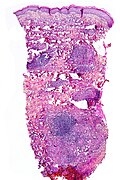

Lichenoid keratosis

General

- Caucasians - middle age or older.

- May be a variant of seborrheic keratosis (with marked inflammation).[21]

Clinical DDx:[21]

- Basal cell carcinoma, squamous cell carcinoma of the skin, melanocytic neoplasm.

Microscopic

Features:[22]

- Hyperkeratosis.

- Parakeratosis.

- Band of inflammatory cells at DE junction (lichenoid inflammation).

- Dead keratinocytes (Civatte bodies).

- Dermal melanophages.

DDx:

- Lichen planus - need clinical correlation (mucosal lesions).

- Drug reaction.

- Cutaneous T-cell lymphoma.

- Regressed melanocytic lesion, esp. malignant melanoma.

- Lichenoid actinic keratosis - has atypical hyperchromatic basal cells - esp. at edge of lesion, usu. in the context of solar elastosis.

Images:

Sign out

SKIN LESION, MID-MIDDLE BACK, PUNCH BIOPSY: - LICHENOID KERATOSIS.

Incompletely excised

SKIN LESION, LEFT CHEST, PUNCH BIOPSY: - LICHENOID KERATOSIS VERSUS ACTINIC KERATOSIS. - NEGATIVE FOR BASAL CELL CARCINOMA. - SEE COMMENT. COMMENT: No eosinophils are apparent. No melanocytic lesion is identified; however, excision of the whole lesion to exclude a partially regressed melanocytic lesion is suggested.